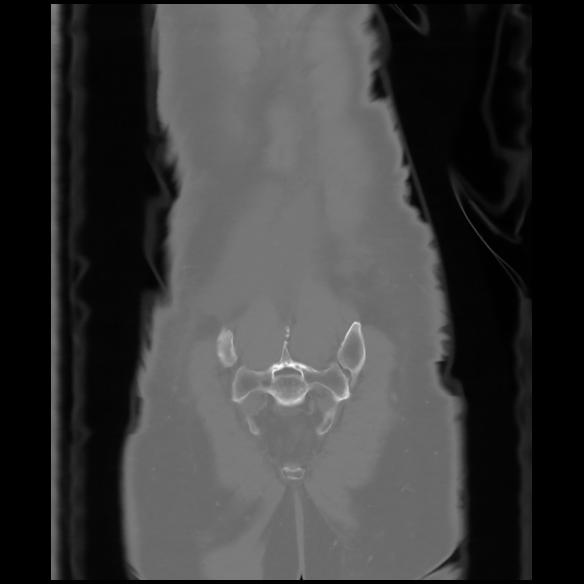

6 CUERPO,CE,Coronal,3.000,CUERPO,Coronal,